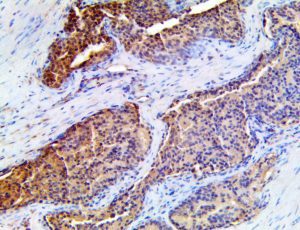

It is the ICU physician who is most likely to witness one of the deadliest manifestations of the abnormal immunological response, the cytokine storm syndrome (CSS). This response is also referred to by some as the cytokine release syndrome (CRS). CSS is characterized by continuous activation and expansion of macrophage and lymphocyte populations, which secrete large amounts of cytokines, causing the cytokine storm. This massive cytokine release is akin to hemophagocytic lymphohistiocytosis (HLH) disease, a syndrome characterized by initial unchecked and persistent activation of cytotoxic T lymphocytes and NK cells.

Clinical and laboratory manifestations of HLH include fever, enlarged liver and/or spleen, neurologic dysfunction, coagulopathy, liver dysfunction, cytopenias (i.e., low levels of erythrocytes, leukocytes, and/or platelets), hypertriglyceridemia, hyperferritinemia, hemophagocytosis, and eventually diminished NK cell activity as the immune system becomes progressively paralyzed. HLH can be familial (primary HLH) or secondary to another disease process (sHLH), such as rheumatic disease, in which it is referred to as macrophage activation syndrome (MAS, characterized by elevated ferritin).